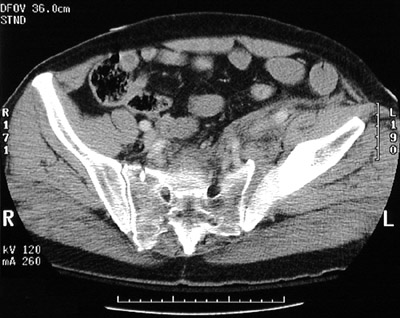

Following a fall, the male whose pelvis is depicted here sustained a

fracture-dislocation

to the left sacroiliac joint with resultant adjacent

soft tissue hemorrhage

.